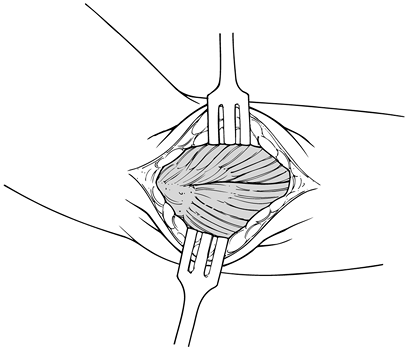

Inspect the underlying extensor tendon mechanism that has been released subperiosteally (Fig. 81.18).

Note any evidence of tears, granulation tissue, or fibrinous

replacement of the tendon. Inspect the radiocapitellar joint and the

overlying synovium.

Figure 81.18. Lateral exposure of the pathology in the ECRB and joint. -

Tears of various degrees and magnitudes

are commonly found on the underside of the extensor carpi radialis

brevis and frequently may penetrate distally to the level of the

lateral compartment of the elbow joint. Therefore, follow the tendon to

the level of the radiocapitellar joint to be sure that the entire

pathology has been observed (Fig. 81.19). If a

tear, granulation tissue, or fibrinous material is not identified in

the extensor carpi radialis brevis, inspect the extensor carpi radialis

longus proximally and the extensor digitorum distally.